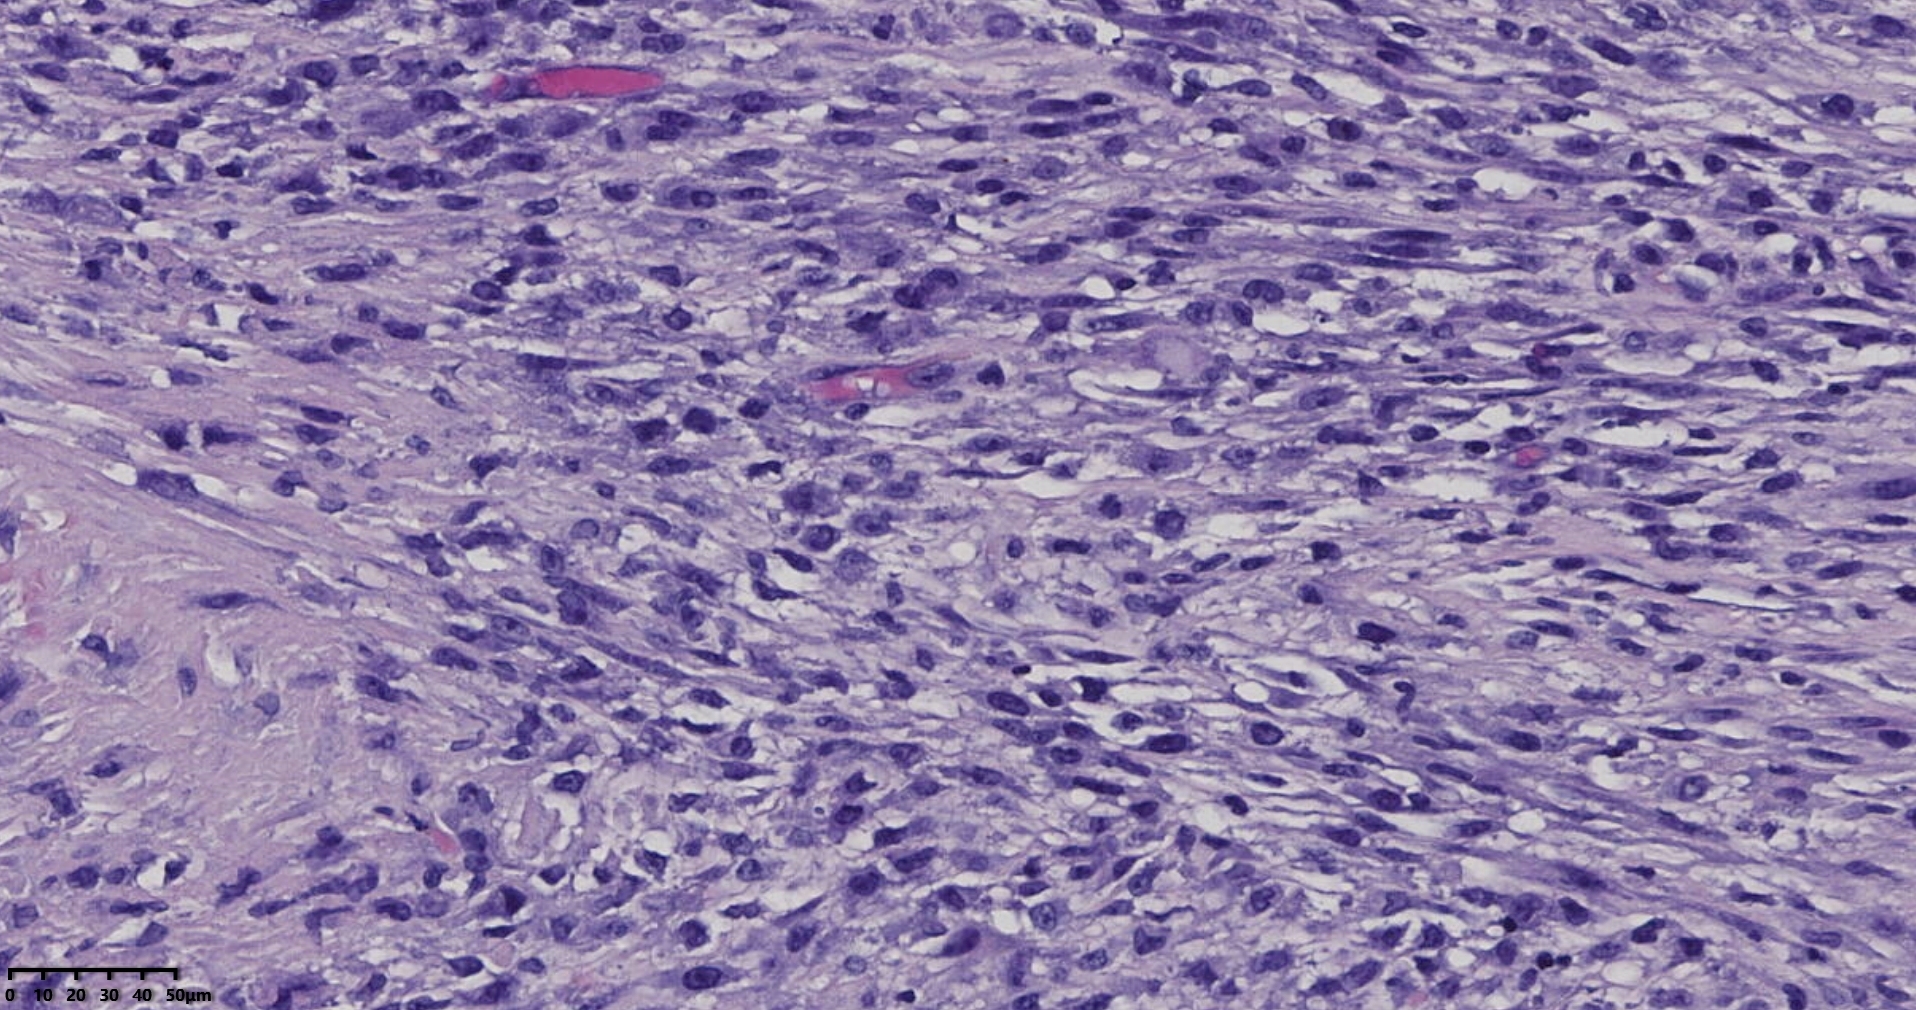

镜下所见小肿物无特殊,大肿物瘤细胞密集,中心区有变性、坏死,瘤细胞核有异型性。大肿物补充取材,发现,部分区域切面灰黄,这个区域,瘤细胞更密集,异型性更显著。肿物边缘有薄层正常平滑肌组织被覆,靠近边缘瘤细胞最密集,局部瘤组织内小血管较丰富。

会诊:考虑平滑肌肉瘤。

北医三院会诊:子宫平滑肌瘤伴红色变性可能性大,建议加做免疫组化及NGS检测进一步明确诊断。